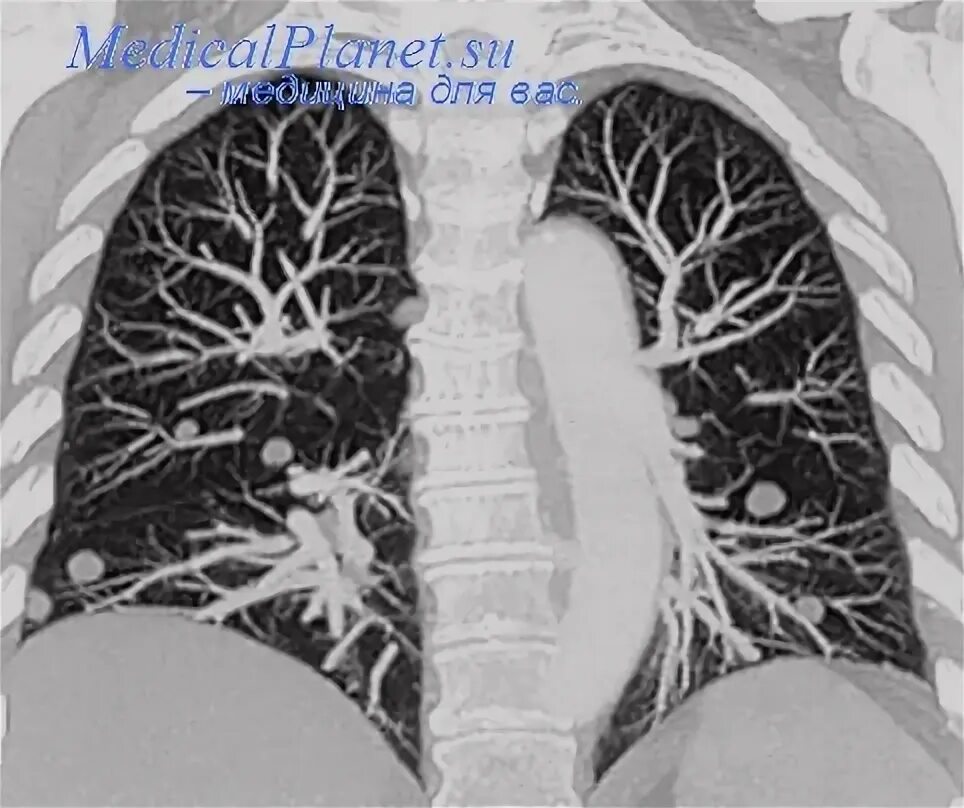

Бронхоаденит это